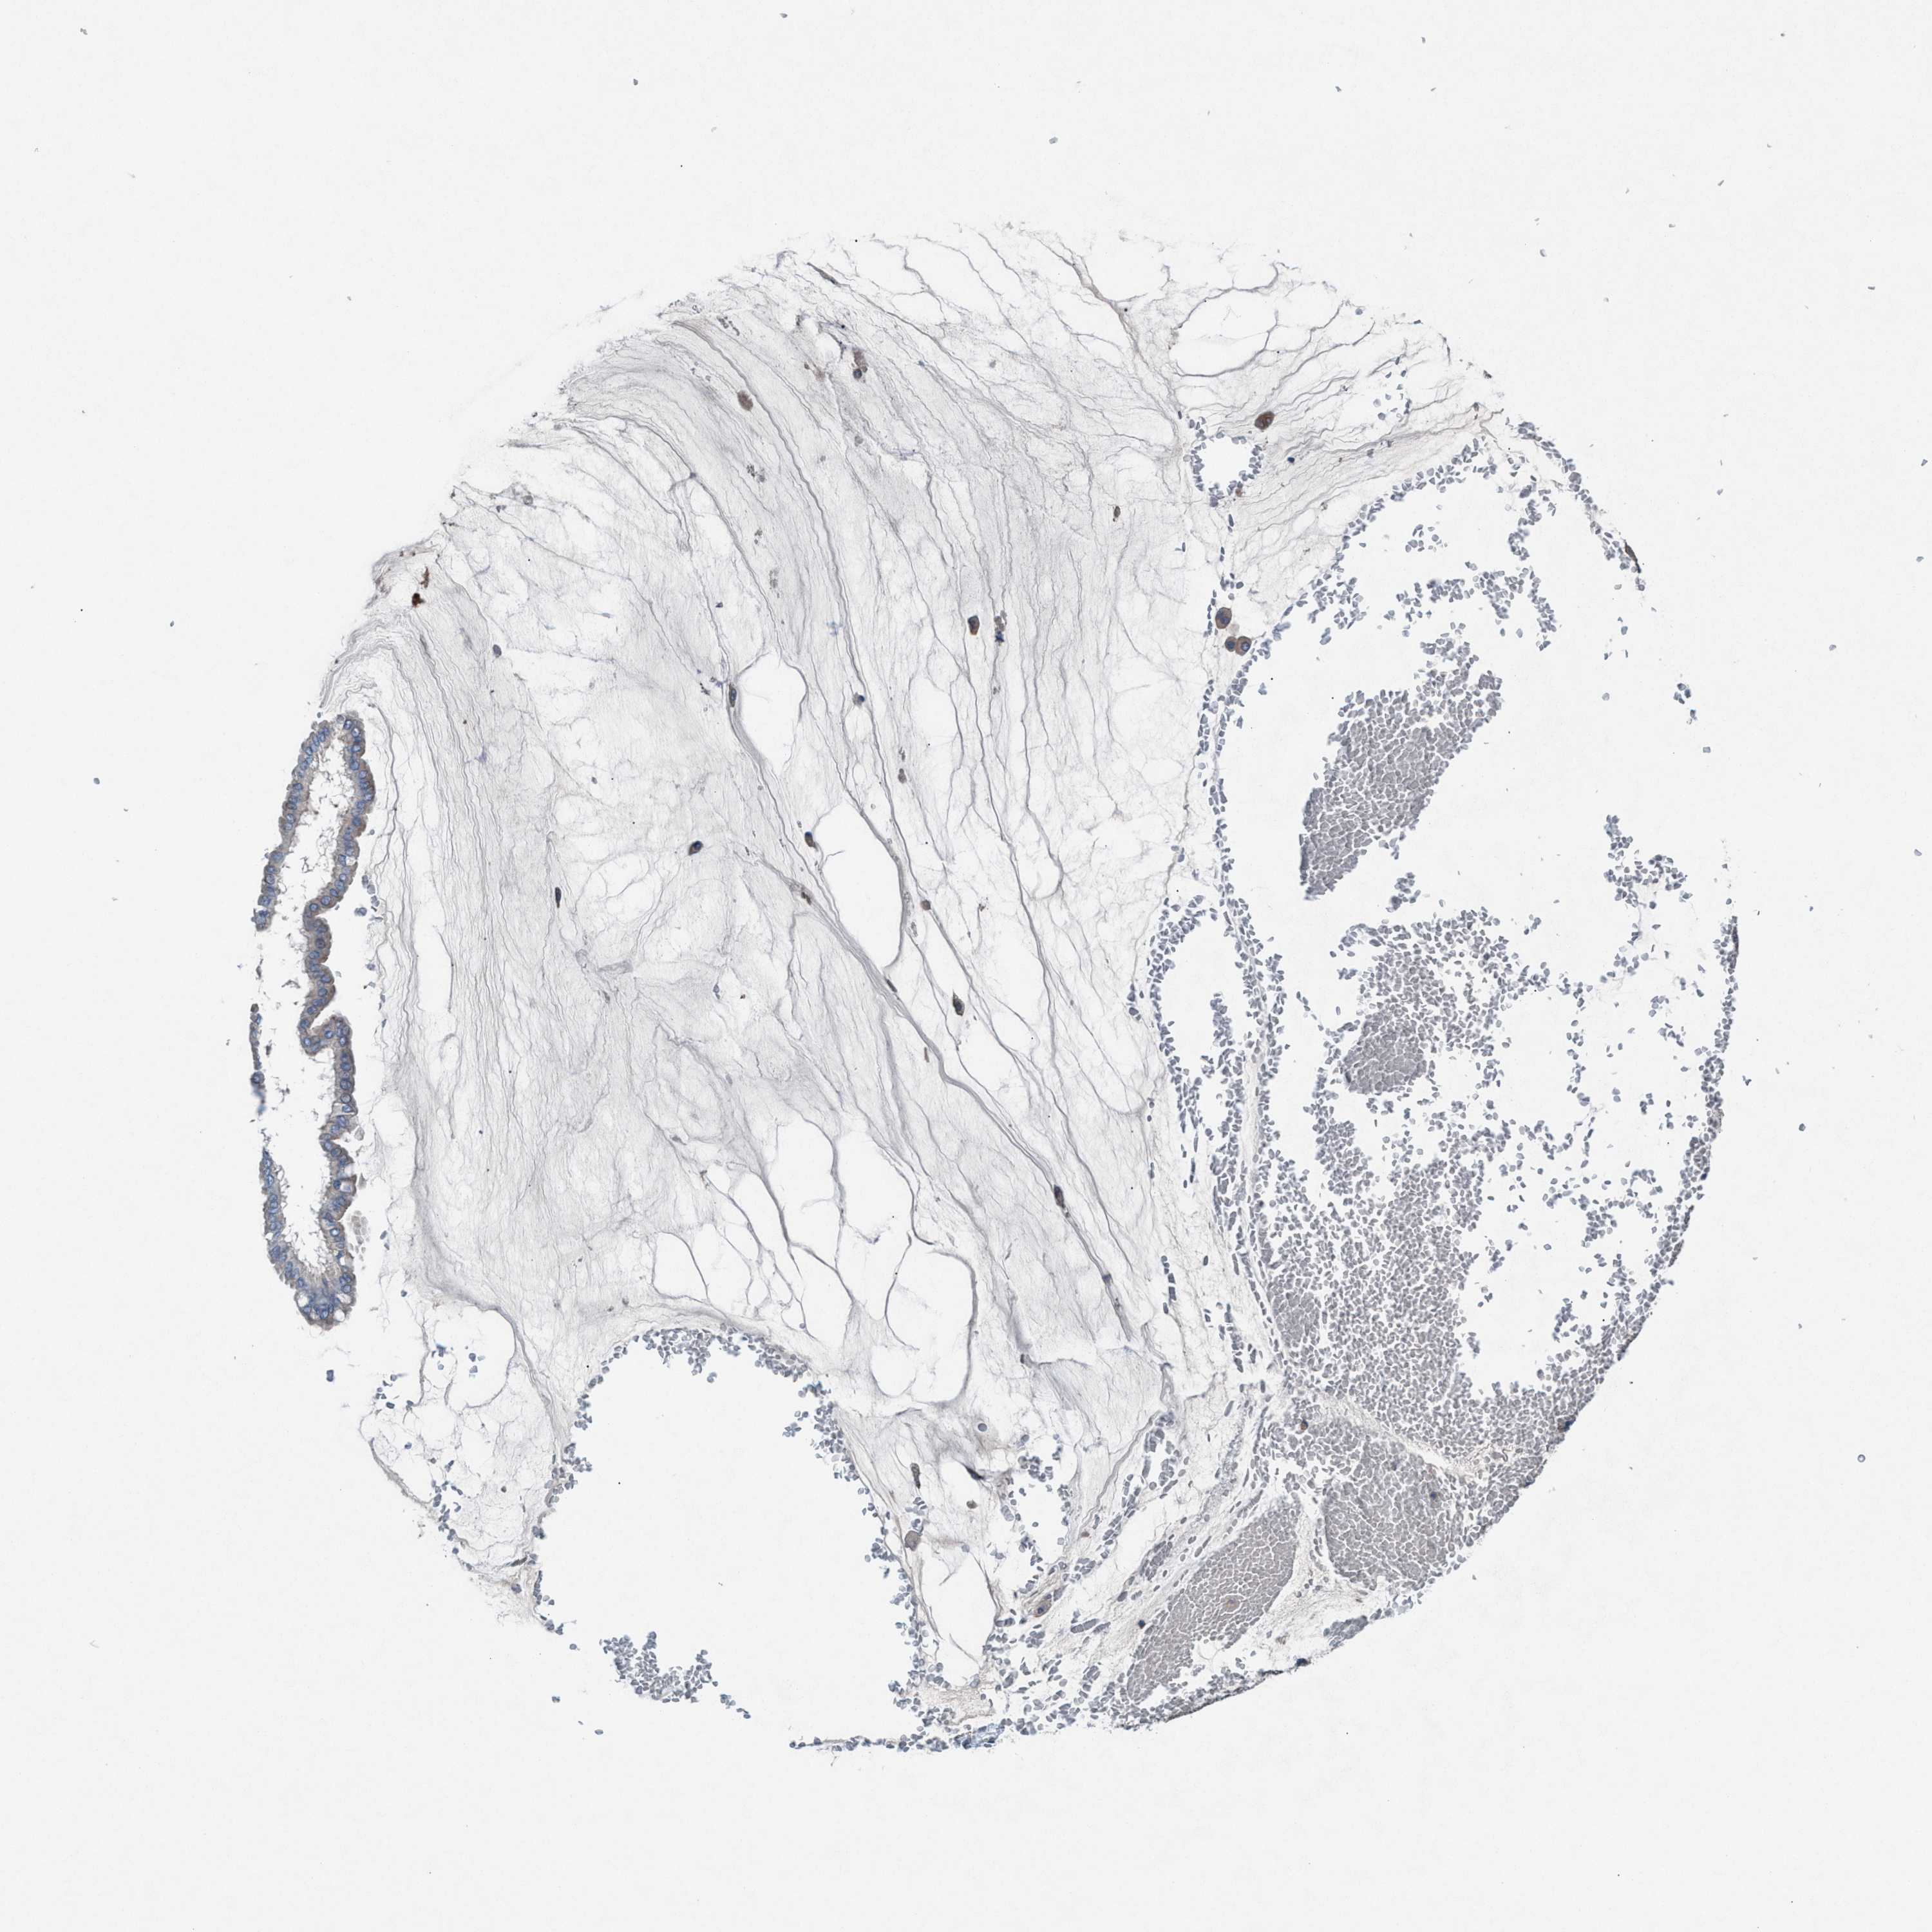

OVARIAN CANCER - Protein expressioni

A mouse-over function shows sample information and annotation data. Click on an image to view it in a full screen mode. Samples can be filtered based on level of antibody staining by selecting one or several of the following categories: high, medium, low and not detected. The assay and annotation is described here.

Note that samples used for immunohistochemistry by the Human Protein Atlas do not correspond to samples in the TCGA dataset.

Antibody stainingi

Antibody staining in the annotated cell types in the current human tissue is reported as not detected, low, medium, or high, based on conventional immunohistochemistry profiling in selected tissues. This score is based on the combination of the staining intensity and fraction of stained cells.

Each image is clickable and will lead to virtual microscopy that enables deeper exploration of all samples and also displays staining intensity scores, fraction scores and subcellular localization as well as patient and tissue information for each sample.

Antibody HPA021598

Staining

High

Medium

Low

Not detected

Intensity

Strong

Moderate

Weak

Negative

Quantity

>75%

75%-25%

<25%

None

Location

Nuclear

Cytoplasmic/membranous

Cytoplasmic/membranous,nuclear

Cystadenocarcinoma, serous, NOS

Carcinoma, endometroid

Cystadenocarcinoma, mucinous, NOS